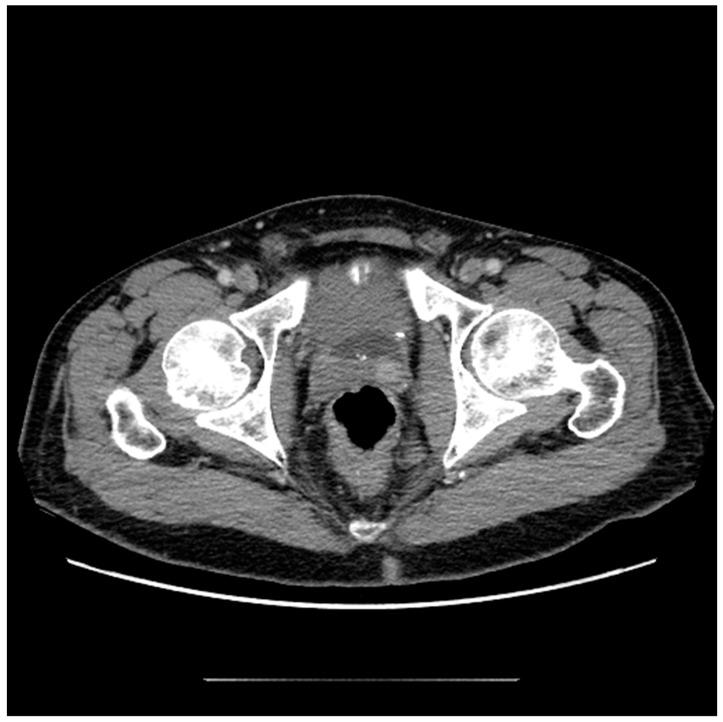

Contemporary Review of Multimodality Imaging of the Prostate Gland.

Tissue changes and the enlargement of the prostate, whether benign or malignant, are among the most common groups of diseases that affect men and can have significant impacts on length and quality of life. The prevalence of benign prostatic hyperplasia (BPH) increases significantly with age and affects nearly all men as they grow older. Other than skin cancers, prostate cancer is the most common cancer among men in the United States. Imaging is an essential component in the diagnosis and management of these conditions. Multiple modalities are available for prostate imaging, including several novel imaging modalities that have changed the landscape of prostate imaging in recent years. This review will cover the data relating to commonly used standard-of-care prostate imaging modalities, advances in newer technologies, and newer standards that impact prostate gland imaging.